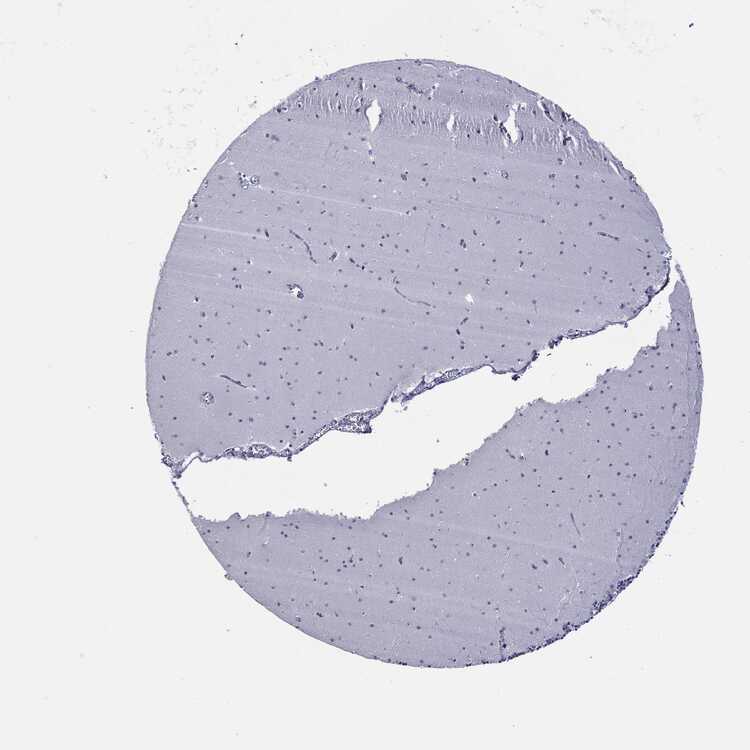

CEREBELLUM - Antibody stainingi

Antibody staining in the annotated cell types in the current human tissue is reported as not detected, low, medium, or high, based on conventional immunohistochemistry profiling in selected tissues. This score is based on the combination of the staining intensity and fraction of stained cells.

Each image is clickable and will lead to virtual microscopy that enables deeper exploration of all samples and also displays staining intensity scores, fraction scores and subcellular localization as well as patient and tissue information for each sample.

Antibody HPA042681Antibody CAB022202Antibody CAB080112

Purkinje cells Not detectedNot detectedNot detected

Cells in granular layer Not detectedNot detectedNot detected

Cells in molecular layer Not detectedNot detectedNot detected